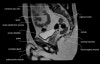

- Axial section

Axial T1 large field of view allows for evaluation of both hips simultaneously, particularly the acetabulae.

Axial PD fat suppressed is sensitive to fluid that may be present with avascular necrosis or stress fractures, while maintaining high a SNR.